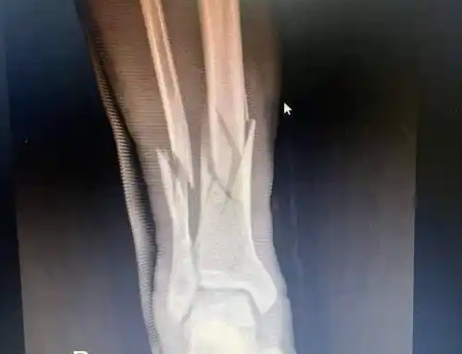

术后康复需要注意那些?

功能锻炼活动以恢复患处肢体的原有生理功能为中心。上肢各种活动要以增加手的握力为重点,下肢以增强其负重、步行能力为重点。 功能锻炼活动要遵照循序渐进的原则。随着骨折部位稳固程度的增加,活动范围应由小渐大,活动次数由少至多,活动强度由弱到强。但自我...

功能锻炼活动以术后康复恢复患处肢体的原有生理功能为中心。上肢各种活动要以增加手的握力为重点,下肢以增强其负重、步行能力为重点。 功能锻炼活动要遵照循序渐进的原则。随着骨折部位稳固程度的增加,活动范围应由小渐大,活动次数由少至多,活动强度...